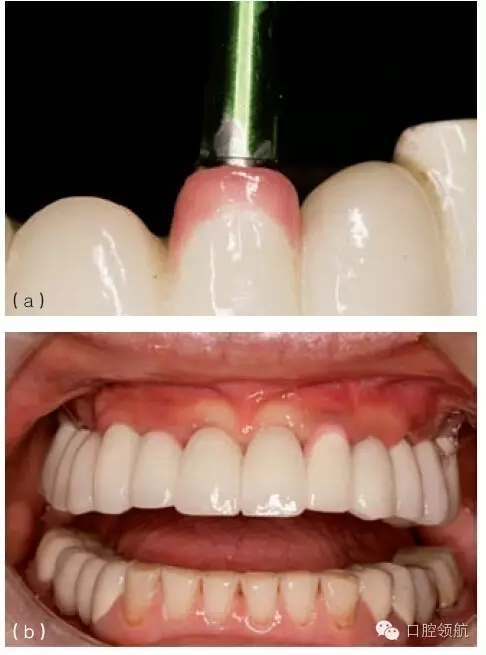

在種植體植入之前,有必要確定最終的修復方案,并且計算放置種植體修復部件所需要的空間。例如,對于單個粘結固位的種植修復體,從種植體平臺到對頜牙,最少需要7mm的空間。這個空間包括以下組成部分:基臺距對頜牙牙合面2mm;對粘結固位來說,即便聚合度非常平行的情況下,也至少需要4.5mm的預備高度,才能滿足固位要求;基臺與種植體交接的拋光肩領需要0.5mm。如果牙合間距離較?。ㄈ?.5~5mm),可以制作螺絲固位修復體(或UCLA的一體化冠)(圖9.23a,b)。實施種植手術時,必須考慮牙齦厚度及牙槽骨的水平。若有需要,可以施行牙槽嵴切除術,以獲得額外的牙合間距離。另外,種植體可以高于、低于或平齊牙槽嵴頂,以便與未來的修復體匹配。但當在修復期間考慮這些問題時,剩下的選擇就非常有限,只能在粘結固位或螺絲固位中選擇一種。有時,可以選磨對頜牙,來獲取少量的修復空間。另外,如果需要恢復垂直高度的話,可以通過升高咬合來獲得牙合間距離。

圖9.23 (a) 頰面觀, 牙合間距離不足(5mm)(相對于粘結固位),需要制作螺絲固位式修復體。(b)牙合 面和舌側(cè)觀,完成的螺絲固位式修復體。